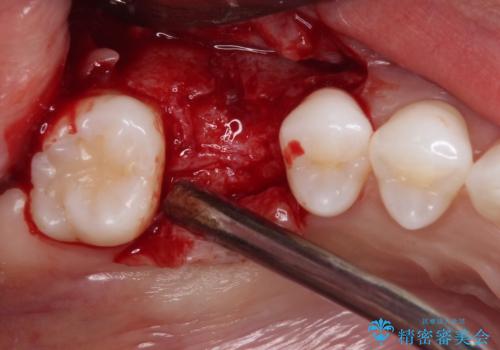

- 歯がほとんどなくなってしまうまで虫歯を放置してしまったとのことで来院された患者様です。

抜歯が必要であることは患者様自身も理解されており、インプラントによる欠損補綴治療を希望されていらっしゃいました。

抜歯前のCTにより、インプラントを埋入するために必要な歯槽骨量が不足することが予想されたため、サイナスソケットリフトにより上顎洞内の粘膜を挙上して、インプラントを埋入することとしました。